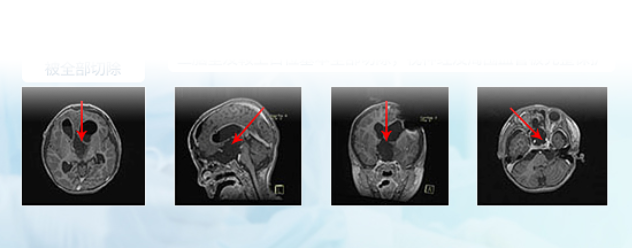

在德国INI国际神经学研究所,经巴特朗菲教授与前国际儿童神经外科协会主席Di Rocco教授曾联合手术,这个孩子的视神经胶质瘤得到了≥大概率的切除程度,达全切,从术前侵袭至双侧额叶及三脑室的较大瘤体,到术后影像上未见瘤体,从几近失明到逐渐地视力恢复接近正常,他的手术效果可以说是教科书级的示范案例。

德国巴教授INI手术结果